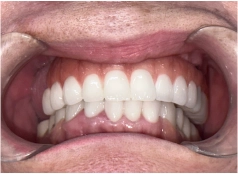

• Tình trạng răng trước đây:Mất răng toàn hàm, dùng hàm tháo lắp lâu năm bị tiêu xương hàm

• Cấy ghép Implant toàn hàm All On 5

• Phục hình răng sứ trên implant

Đặt niềm tin vào đội ngũ bác sĩ I-Dent giúp quá trình trồng răng Implant của cô Liên diễn ra hoàn toàn thuận lợi. Kết quả cuối cùng thành công đúng như cô mong muốn. Hàm răng mới chắc khỏe, giúp cô ăn uống thoải mái mà không còn lo lắng bị đau nhức hay rơi rớt như khi dùng hàm tháo lắp.